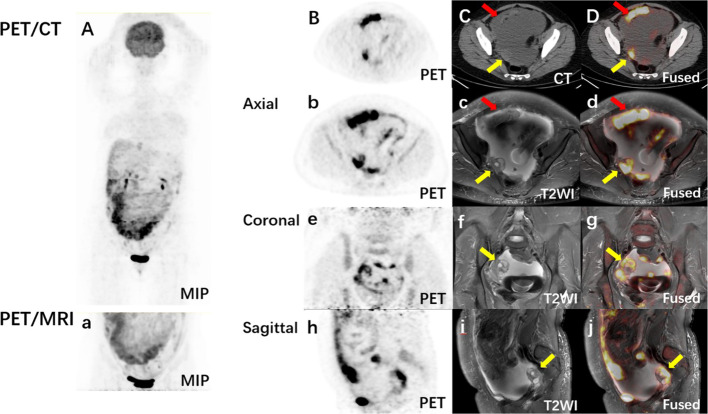

Background: Comparing to PET/CT, integrative PET/MRI imaging provides superior soft tissue resolution. This study aims to evaluate the added value of regional delayed 18F-FDG PET/MRI-assisted whole-body 18F-FDG PET/CT in diagnosing malignant ascites patients.

Results: The final diagnosis included 22 patients with ovarian cancer (n = 11), peritoneal cancer (n = 3), colon cancer (n = 2), liver cancer (n = 2), pancreatic cancer (n = 2), gastric cancer (n = 1), and fallopian tube cancer (n = 1). The diagnosis of the primary tumor using whole-body PET/CT was correct in 11 cases. Regional PET/MRI-assisted whole-body PET/CT diagnosis was correct in 18 cases, including 6 more cases of ovarian cancer and 1 more case of fallopian tube cancer. Among 4 cases that were not diagnosed correctly, 1 case had the primary tumor outside of the PET/MRI scan area, 2 cases were peritoneal cancer, and 1 case was colon cancer. The diagnostic accuracy of regional PET/MRI-assisted whole-body PET/CT was higher than PET/CT alone (81.8% vs. 50.0%, κ 2 = 5.14, p = 0.023). The primary tumor conspicuity score of PET/MRI was higher than PET/CT (3.67 ± 0.66 vs. 2.76 ± 0.94, P < 0.01). In the same scan area, more metastases were detected in PET/MRI than in PET/CT (156 vs. 86 in total, and 7.43 ± 5.17 vs. 4.10 ± 1.92 per patient, t = 3.89, P < 0.01). Lesion-to-background ratio in PET/MRI was higher than that in PET/CT (10.76 ± 5.16 vs. 6.56 ± 3.45, t = 13.02, P < 0.01).

Conclusion: Comparing to whole-body PET/CT alone, additional delayed regional PET/MRI with high soft tissue resolution is helpful in diagnosing the location of the primary tumor and identifying more metastases in patients with malignant ascites. Yet larger sample size in multicenter and prospective clinical researches is still needed.